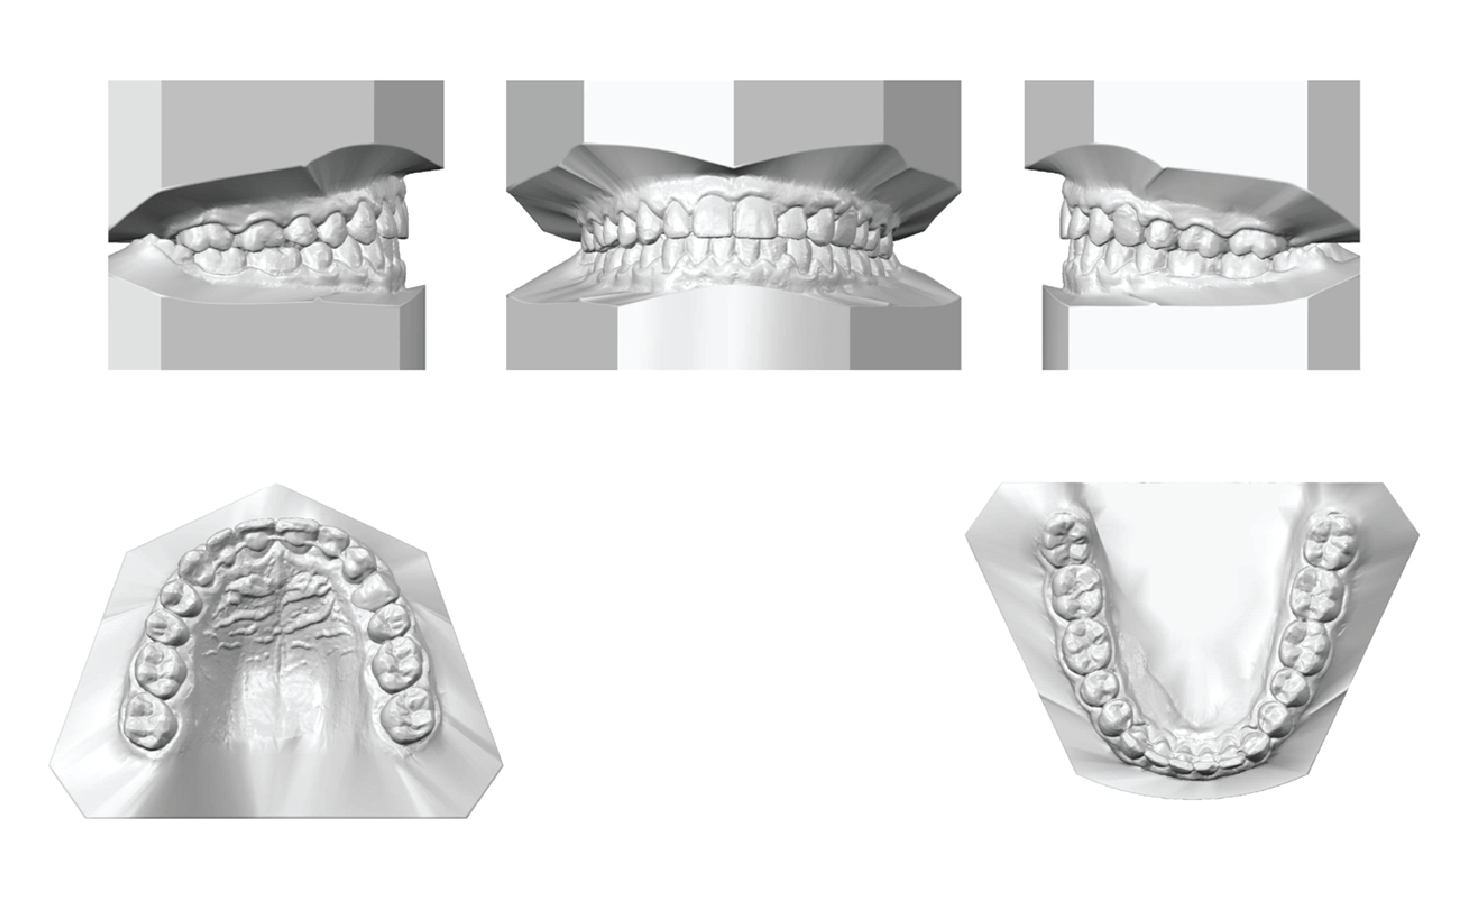

An analysis of the cast at the end of treatment revealed the following outcomes:

1) The maxillary and mandibular dentitions demonstrated mild transverse development, with a slight increase in inter-molar width of 0.4 mm and inter-canine width of 1.2 mm in the maxilla. In the mandible, there was no increase in inter-molar width; however, the inter-canine width increased by 2.3 mm (Figure 6).

2) A Class I canine relationship was achieved on the left side, and the molar relationship was maintained on this side. On the right side, both Class I molar and canine relationships were maintained.

3) The crowding in the mandibular dental arch was eliminated.Â

4) The open bite on the left side was closed, resulting in a normal overbite of 2 mm and an overjet of 1.5 mm.Â

5) Dental marginal ridge were leveled

Figure 6: Post-treatment digital casts. Post-treatment digital cast analysis showed Class I molar and canine relationships on both sides. And ideal overbite and overjet were established, marginal ridges were leveled, the dentition was aligned, and both arches were developed transversely.